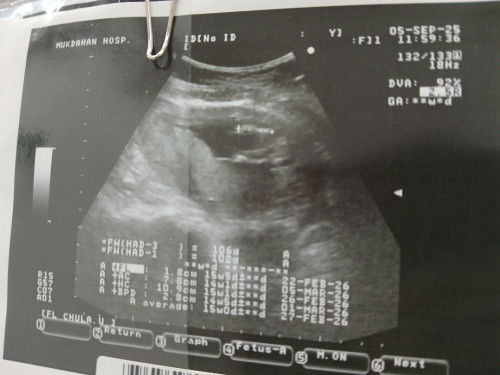

แบบนี้น้องเป็นผู้หญิงหรือผู้ชายค่ะหมอบอกว้าไม่แน่ใจว่าน้แงจะเป็นผู้ชายรึป่าวค่ะ